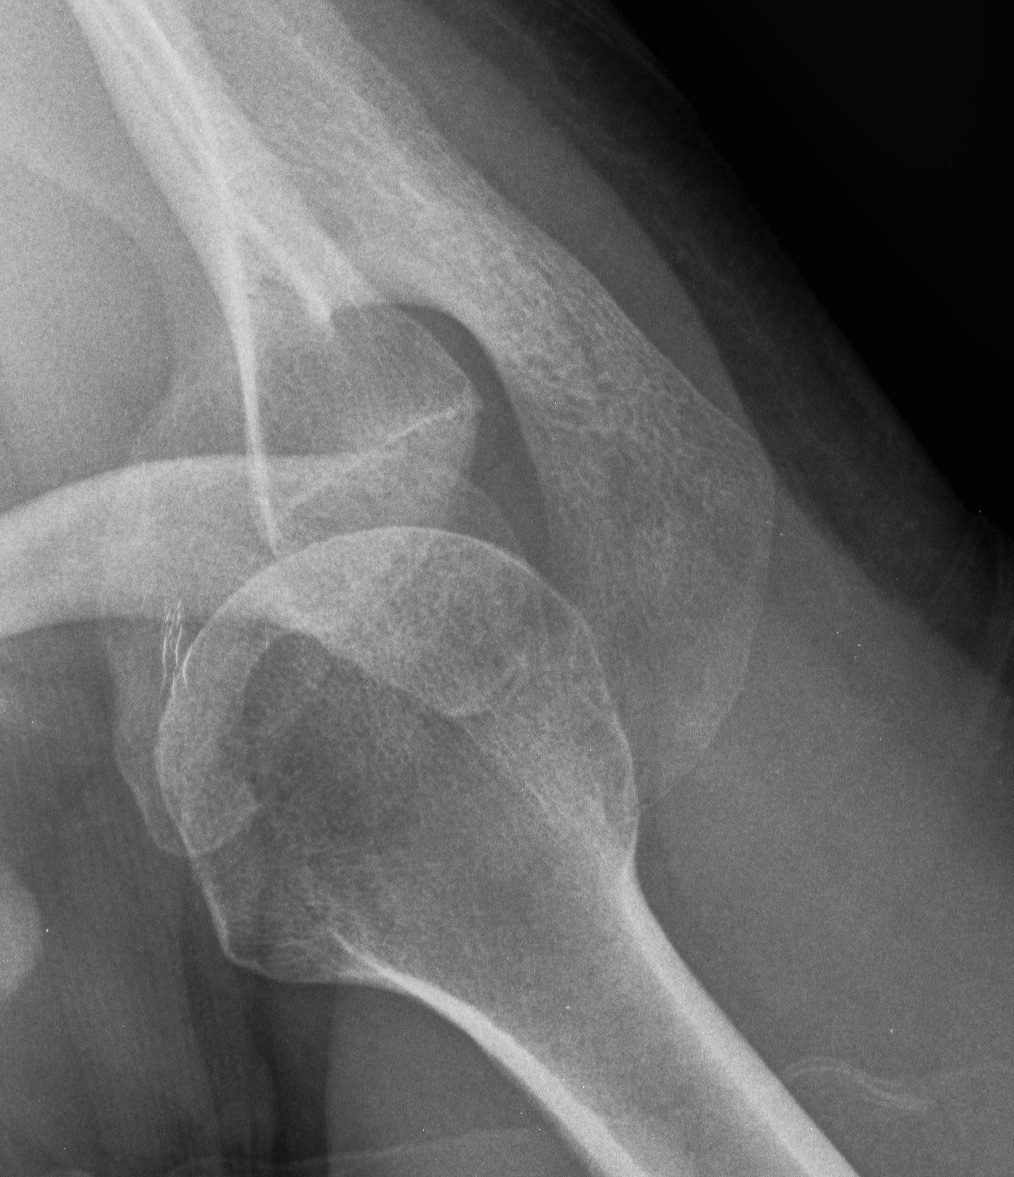

Open reduction +/- glenoid bone graft +/- Hill Sachs allograft +/- rotator cuff repair

Humeral head replacement + glenoid autograft + rotator cuff repair

Post humeral head replacement / glenoid autograft / rotator cuff repair

Rotator cuff failure and development of anterosuperior escape

Reverse TSA +/- glenoid bone graft

Chronic locked with large Hill Sachs treated with rTSA + glenoid bone graft

Chronic locked with large Hill Sachs and normal glenoid treated with rTSA + glenoid bone graft